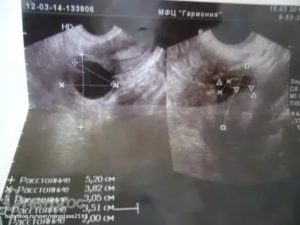

Наблюдение за этим процессом осуществляется при помощи такого простого метода как ультразвуковое исследование. Обычного это необходимо на этапе планирования и в первые недели наступившей беременности, а также при лечении бесплодия или прочих патологиях яичников.

Самым благоприятным временем по дням цикла для исследования является вторая неделя (7-10 день с момента последней менструации). При необходимости более точного контроля работы яичников и развития фолликулов УЗИ проводят троекратно, примерно по следующей схеме:

Размеры желтого тела сразу после овуляции составляют около 12 – 20 миллиметров. С каждым днем цикла ЖТ увеличивается в размерах, которые достигают своего пика к концу цикла, на 19-28 день. В это время нормальный размер ЖТ – 23-29 мм.